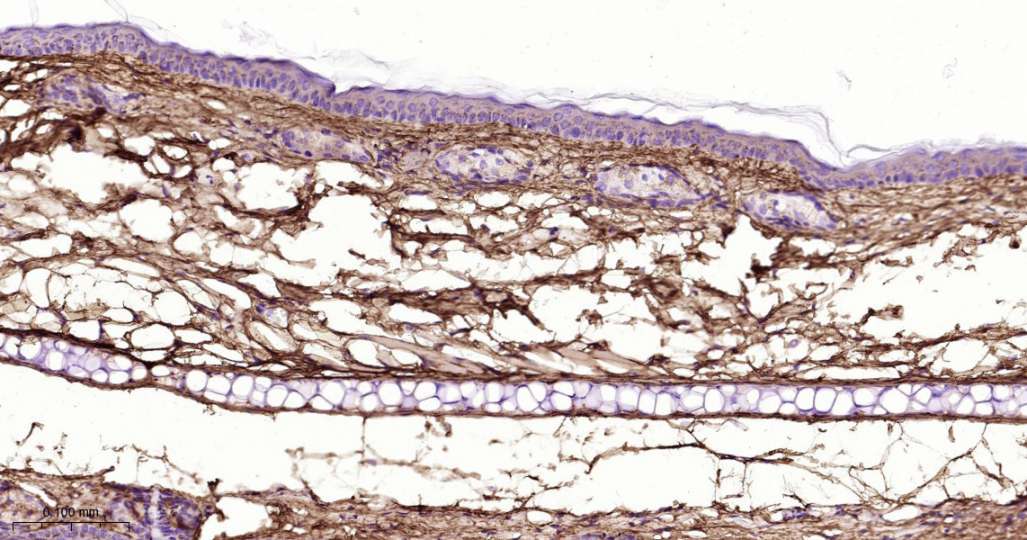

Immunohistochemical analysis of paraffin embedded Mouse skin tissue slide using IHC0654 (Collagen III Kit).

Immunohistochemical analysis of paraffin embedded Rat skin tissue slide using IHC0654 (Collagen III Kit).